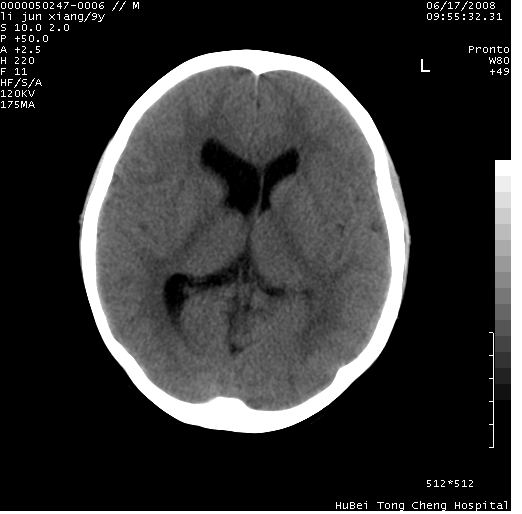

患儿 男,9岁。既往有“脑积水,脑萎缩?”病史(无影像检查资料),现无明显不适。其家长要求ct检查。

颅脑ct轴位平扫(层厚、层距均为10mm),图像如下:

只是双侧脑室不对称,其它未见异常啊